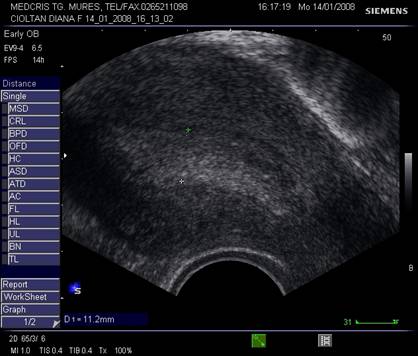

Fig. nr.371. Folicul selectat ziua a XI a de ciclu menstrual, la ecografia transvaginala

Fig. nr.372. Folicul preovulator , in care se remarca

cumulus oophorus ( sageata, eco transv.)

Dupa ziua a 5-7, un folicul ovarian devine dominant , fata de ceilalti ce devin atretici. In ziua 10 -a - 11-a foliculul depaseste 12 mm diametru. Cresterea foliculara de 2 - 3 mm/zi ne duce la un folicul preovulator de cca 21 mm diametru (24 - 26 mm). Doi foliculi dominanti au fost identificati in 10% din ciclurile spontane [8].

Deoarece foliculii sunt ovoidali, diametrul mediu conteaza pentru foliculometria, dupa masurarea a 3 diametre si impartirea la 3.[6]